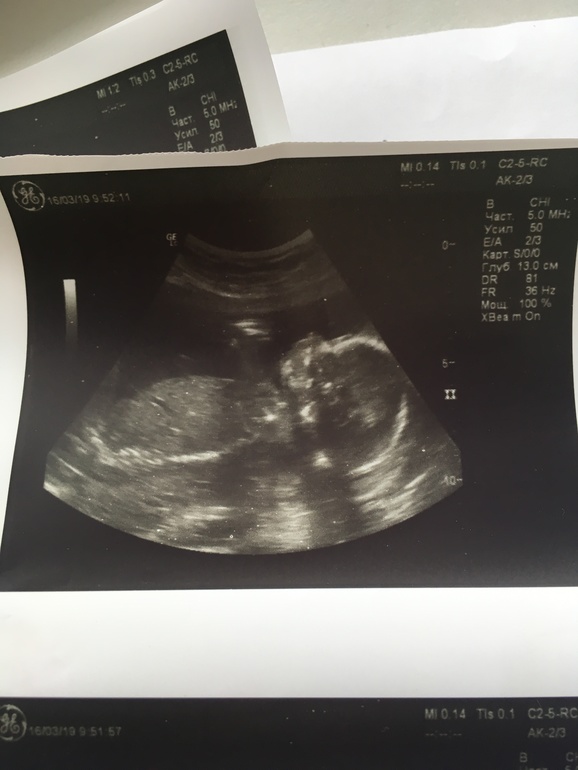

С малышком все отлично - весит уже 390 г, чсс 133 удара (малыш все узи лежал спокойно и изредка потягивался), воды чистые и объем нормальный, прошлась по внутренним органам - все отлично) Но одно только огорчило малость - однократное обвитие пуповиной, не тугое, но все же.

Идем срок в срок - и по М и по УЗИ - 20 неделек.

И фото "домика" на память